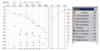

45-årig trommeslager i et heavy metal band, der ellers er sund og rask henvender sig til øre-næse- hals-lægen, da han har fået tiltagende problemer med at høre på venstre øre samt tinnitus på venstre øre. Han oplever desuden kortvarig ubalance, hvis han vender sig hurtigt rundt. Patienten har ikke slået hovedet, og han har ikke hovedpine.

Han får lavet nedenstående audiogram samt tympanometri.

1. Angiv supplerende spørgsmål til anamnesen (max 20 ord).

- Der skal spørges ind til erhvervsmæssig støjpåvirkning og varighed af denne samt arvelige høretab i familien.

- Fuldt point, hvis angivelse af: Støjanamnese, varighed og disposition til høretab.

Essay

45-årig trommeslager i et heavy metal band, der ellers er sund og rask henvender sig til øre-næse- hals-lægen, da han har fået tiltagende problemer med at høre på venstre øre samt tinnitus på venstre øre. Han oplever desuden kortvarig ubalance, hvis han vender sig hurtigt rundt. Patienten har ikke slået hovedet, og han har ikke hovedpine.

Han får lavet nedenstående audiogram samt tympanometri.

2. Hvilket type høretab er der tale om?

- Perceptivt asymmetrisk høretab.

- Fuldt point for angivelse af både asymmetri og perceptivt høretab.

- Angivelse af perceptivt høretab vigtigst.

Essay

45-årig trommeslager i et heavy metal band, der ellers er sund og rask henvender sig til øre-næse- hals-lægen, da han har fået tiltagende problemer med at høre på venstre øre samt tinnitus på venstre øre. Han oplever desuden kortvarig ubalance, hvis han vender sig hurtigt rundt. Patienten har ikke slået hovedet, og han har ikke hovedpine.

Han får lavet nedenstående audiogram samt tympanometri.

3. Angiv værdien af SRT for det højre øre og DS for det venstre øre incl. Enheder.

- SRT hø: 5 dB el. 5 dBHL – begge accepteres

- DS: 76 % (OK hvis de angiver værdier mellem 75-79%)

Essay

45-årig trommeslager i et heavy metal band, der ellers er sund og rask henvender sig til øre-næse- hals-lægen, da han har fået tiltagende problemer med at høre på venstre øre samt tinnitus på venstre øre. Han oplever desuden kortvarig ubalance, hvis han vender sig hurtigt rundt. Patienten har ikke slået hovedet, og han har ikke hovedpine.

Han får lavet nedenstående audiogram samt tympanometri.

4. Ang. en sandsynlig diagnose for det højresidige høretab.

Støj betinget høretab.

Essay

45-årig trommeslager i et heavy metal band, der ellers er sund og rask henvender sig til øre-næse- hals-lægen, da han har fået tiltagende problemer med at høre på venstre øre samt tinnitus på venstre øre. Han oplever desuden kortvarig ubalance, hvis han vender sig hurtigt rundt. Patienten har ikke slået hovedet, og han har ikke hovedpine.

Han får lavet nedenstående audiogram samt tympanometri.

5. Ang. en sandsynlig diagnose for det venstresidige høretab

- Sandsynligt retrocochleært høretab – muligt vestibularis schwanom/acusticus neurimom eller høretab af ukendt årsag.

- Perceptivt høretab som svar kan accepteres med 1 ud af 2 point, men det er mindre præcist end eks. retrocochleært høretab, der bør mistænkes her og derfor anføres som svar.

Essay

45-årig trommeslager i et heavy metal band, der ellers er sund og rask henvender sig til øre-næse- hals-lægen, da han har fået tiltagende problemer med at høre på venstre øre samt tinnitus på venstre øre. Han oplever desuden kortvarig ubalance, hvis han vender sig hurtigt rundt. Patienten har ikke slået hovedet, og han har ikke hovedpine.

Han får lavet nedenstående audiogram samt tympanometri.

6. Hvad er de forventede fund ved otoskopi på højre og venstre øre (max 10 ord)?

- Normalt udseende trommehinde eller intakt trommehinde på begge ører.

- Bemærkning om at venstre sides kan være let atrofisk pga. øget compliance accepteres

Essay

45-årig trommeslager i et heavy metal band, der ellers er sund og rask henvender sig til øre-næse- hals-lægen, da han har fået tiltagende problemer med at høre på venstre øre samt tinnitus på venstre øre. Han oplever desuden kortvarig ubalance, hvis han vender sig hurtigt rundt. Patienten har ikke slået hovedet, og han har ikke hovedpine.

Han får lavet nedenstående audiogram samt tympanometri.

7. Giv forslag til supplerende udredning og undersøgelse af patienten (max 20 ord).

- MR-scanning af fossa posterior/hørenerver

- Også OK at skrive cerebrum og/eller ABR- undersøgelse hjernestammeaudiometri samt vestibulærundersøgese eks. vHiT, og undersøgelse af kranienerver/otoneurologisk undersøgelse.

- Vigtigst er MR.

- ABR = Auditory Brainstem Response*

- VHIT = Video Head Impulse Test*

- Skema med pointgivning vedlagt på dette sidste delspørgsmål*.